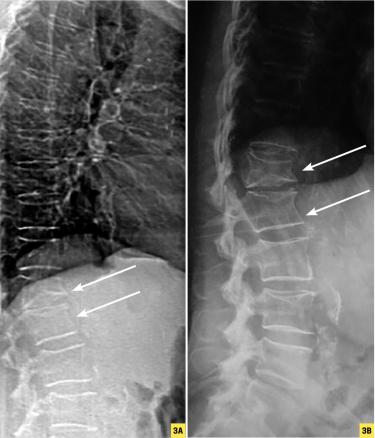

Rachis en VFA (Vertebral Fracture Assessment). B. Cliché standard pour comparaison.